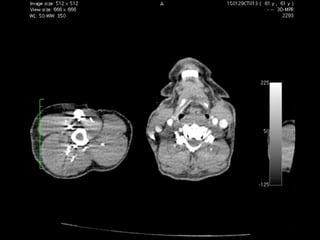

74 yo Female

Chronic Cought, HHD, ASHD

Heavy breath during last 3 mo

Family history (+)